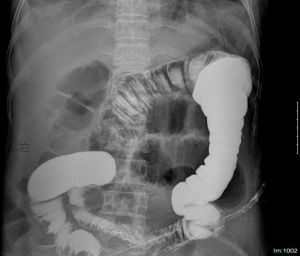

消化性潰瘍、炎症性腸道病、腸道憩室、腸道腫瘤、腸系膜缺血性疾病、絞窄性腸梗阻、嵌頓疝及醫源性、自發性、外傷性腸穿孔。1、十二指腸潰瘍穿孔多有長期潰瘍病史,疼痛初始部位位於上腹部或劍突下,很快波及全腹,但仍以上腹部為重。2、結直腸腫瘤穿孔結腸癌患者可以有腹痛、貧血、腹部包塊、粘液血便等症狀;直腸癌患者可以有便意頻繁、排便習慣改變、大便變形變細、大便帶血等直腸刺激、腸腔狹窄、癌腫破潰感染症狀。穿孔部位往往位於腫瘤造成狹窄處或者梗阻近端腸管處。腹部CT檢查對本病有提示。3、絞窄性腸梗阻穿孔當腸梗阻伴有腸壁血運障礙,腸管發生缺血壞死時,可出現腸穿孔。絞窄性腸梗阻預後嚴重,並必須及早進行手術治療。有下列表現者,應考慮絞窄性腸梗阻的可能:①腹痛發作急驟,起始即為持續性劇烈疼痛,或在陣發性加重之間仍有持續性疼痛。②病情發展迅速,早期出現休克,抗休克治療後改善不顯著。③有明顯腹膜刺激征,體溫上升、脈率增快、白細胞計數增高。④腹脹不對稱,腹部有局部隆起或觸及有壓痛的腫塊(脹大的腸拌)。⑤嘔吐出現早、劇烈而頻繁。嘔吐物、胃腸減壓抽出液、肛門排出物為血性,或腹腔穿刺抽出血性液體。⑥經積極非手術治療而症狀體徵無明顯改善。⑦腹部X線檢查見孤立、突出脹大的腸拌、不因時間而改變位置。4、腸道炎症性疾病穿孔克羅恩病病因不清,與自身免疫有關,可侵及胃腸道的任何部位,多發生於末端迴腸,呈節段性分布。臨床表現與發病急緩,病變部位和範圍以及有無併發症有關。起病常較緩慢,病史多較長。主要症狀為瀉、腹痛、低熱、體重下降等。便隱血可呈陽性,一般無便血。腹痛常位於右下腹或臍周,一般為痙攣性痛,多不嚴重,常伴局部輕壓痛。當有慢性潰瘍穿透、腸內瘺和粘連形成時,可出現腹內包塊。部分病人出現不全腸梗阻。穿孔的發生率為1~2%,90%發生在末端迴腸,10%發生在空。結腸鏡檢、鋇灌腸檢查有助於診斷。急性出血性腸炎腸管急性炎症病變,病因不清,血便為主要症狀。主要在空腸和迴腸,結腸與胃少見。嚴重可發生出血、壞死、穿孔。臨床表現以急性腹痛、腹脹嘔吐腹瀉、便血及全身中毒症狀為主。腸結核

根據病史、症狀體徵、X線檢查可發現膈下游離氣體、腹部超聲、CT等檢查,不難診斷。但診斷過程中一定要明確穿孔部位、穿孔病因來指導治療。